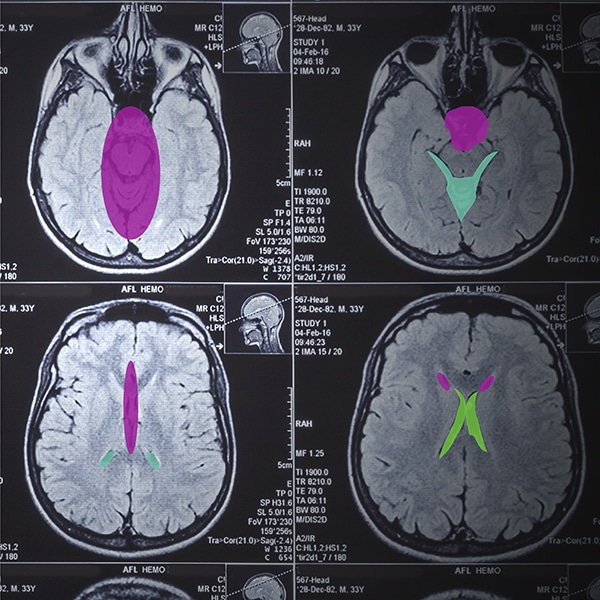

DICOM Medical Imaging Dataset for Advanced AI/ML Applications in Healthcare

De-identified DICOM image datasets with preserved metadata—and optional radiology study reports—to accelerate model training, validation, and clinical research.

Shaip offers AI-ready DICOM medical imaging datasets designed to help healthcare AI teams build, train, and validate robust models for diagnosis, triage, and decision support—using de-identified data that preserves clinical value.

• Total studies:10M+

• Top geographies (by studies): USA, Brazil, and India

• Modalities represented: CR, CT, US, DX, MR, MG, OT, RF, NM, Mammography

• Body parts represented: Chest, Abdomen, Head, Spine, Neck, Heart, & more